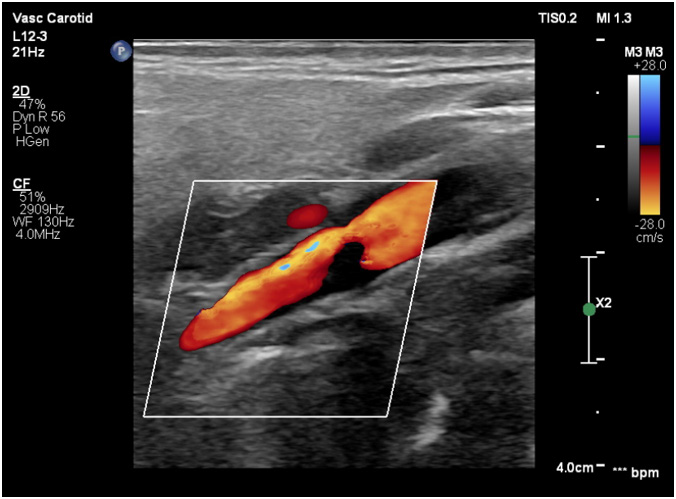

Via native and contrast CT scan intracranial hemorrhage was excluded and the contrast CT scan revealed a thrombus in the left internal carotid artery (Figure 1&2). Doppler ultrasound was also performed which showed a carotid stenosis, caused by a mural thrombus (Figure 3). Treatment with tissue plasminogen activator Actilyse was initiated. The total dose was 63 mg, 6 mg of which administered as a bolus i.v. injection and the remaining 57 mg were given as a continuous infusion for one hour. In the next 24 hours the patient received a heparin infusion, according to the aPTT values.